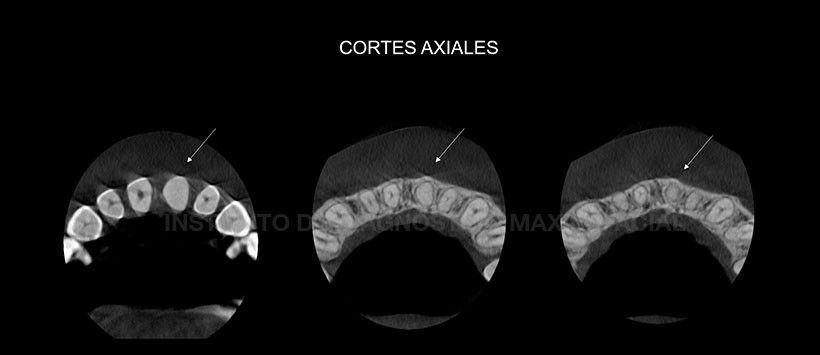

Posteriormente se le realizo una tomografía volumétrica de haz cónico de campo pequeño (En los cortes axiales, transaxiales y tangenciales) donde no si visualiza el conducto radicular en toda la extensión de la pieza 21. Así mismo se pudo apreciar una disminución de la longitud radicular de esta pieza, en relación a su contraparte (Pieza 1.1), dando un indicio de una leve reabsorción radicular externa. (Figura 2, Figura 3 y Figura 4)